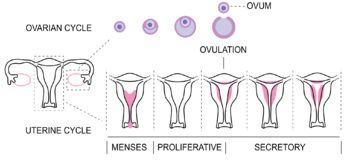

The menstrual cycle is governed by hormonal changes.[6] These changes can be altered by using hormonal birth control to prevent pregnancy.[9] Each cycle can be divided into three phases based on events in the ovary (ovarian cycle) or in the uterus (uterine cycle).[1] The ovarian cycle consists of the follicular phase, ovulation, and luteal phase whereas the uterine cycle is divided into menstruation, proliferative phase, and secretory phase.

The menstrual cycle can be described by the ovarian or uterine cycle. The ovarian cycle describes changes that occur in the follicles of the ovary whereas the uterine cycle describes changes in the endometrial lining of the uterus. Both cycles can be divided into three phases. The ovarian cycle consists of the follicular phase, ovulation, and the luteal phase whereas the uterine cycle consists of menstruation, proliferative phase, and secretory phase.[1]

Follicular phase

The follicular phase is the first part of the ovarian cycle. During this phase, the ovarian follicles mature and get ready to release an egg.[1] The latter part of this phase overlaps with the proliferative phase of the uterine cycle.

Through the influence of a rise in follicle stimulating hormone (FSH) during the first days of the cycle, a few ovarian follicles are stimulated.[63] These follicles, which were present at birth[63] and have been developing for the better part of a year in a process known as folliculogenesis, compete with each other for dominance. Under the influence of several hormones, all but one of these follicles will stop growing, while one dominant follicle in the ovary will continue to maturity. The follicle that reaches maturity is called a tertiary, or Graafian, follicle, and it contains the ovum.[63]

Ovulation

Uterine cycle

The uterine cycle has three phases.[74]

Menstruation

Proliferative phase

Secretory phase

The secretory phase is the final phase of the uterine cycle and it corresponds to the luteal phase of the ovarian cycle. During the secretory phase, the corpus luteum produces progesterone, which plays a vital role in making the endometrium receptive to implantation of the blastocyst and supportive of the early pregnancy, by increasing blood flow and uterine secretions and reducing the contractility of the smooth muscle in the uterus;[84] it also has the side effect of raising the woman's basal body temperature.[85]